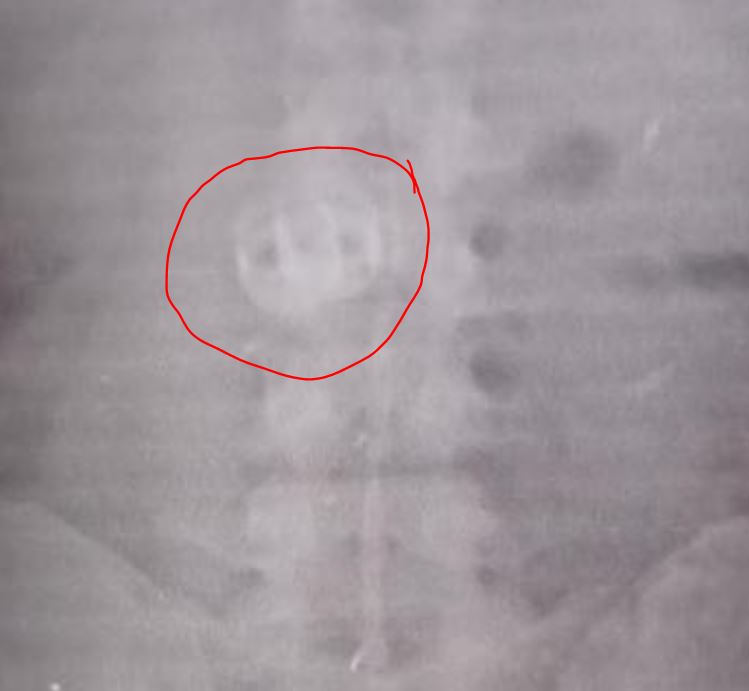

E aí veio a surpresa, um exame de radiografia mostrou as alianças roubadas dentro do estômago do assaltante. Os homens foram encaminhados à delegacia e autuados por roubo.